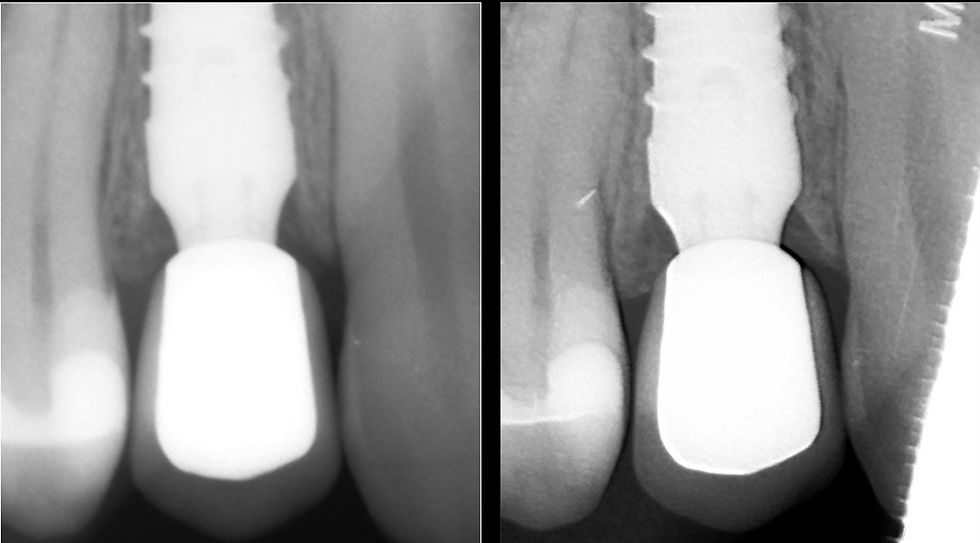

Radiographic images of the implant and the crown in place, at the time of the insertion and after 2 years.